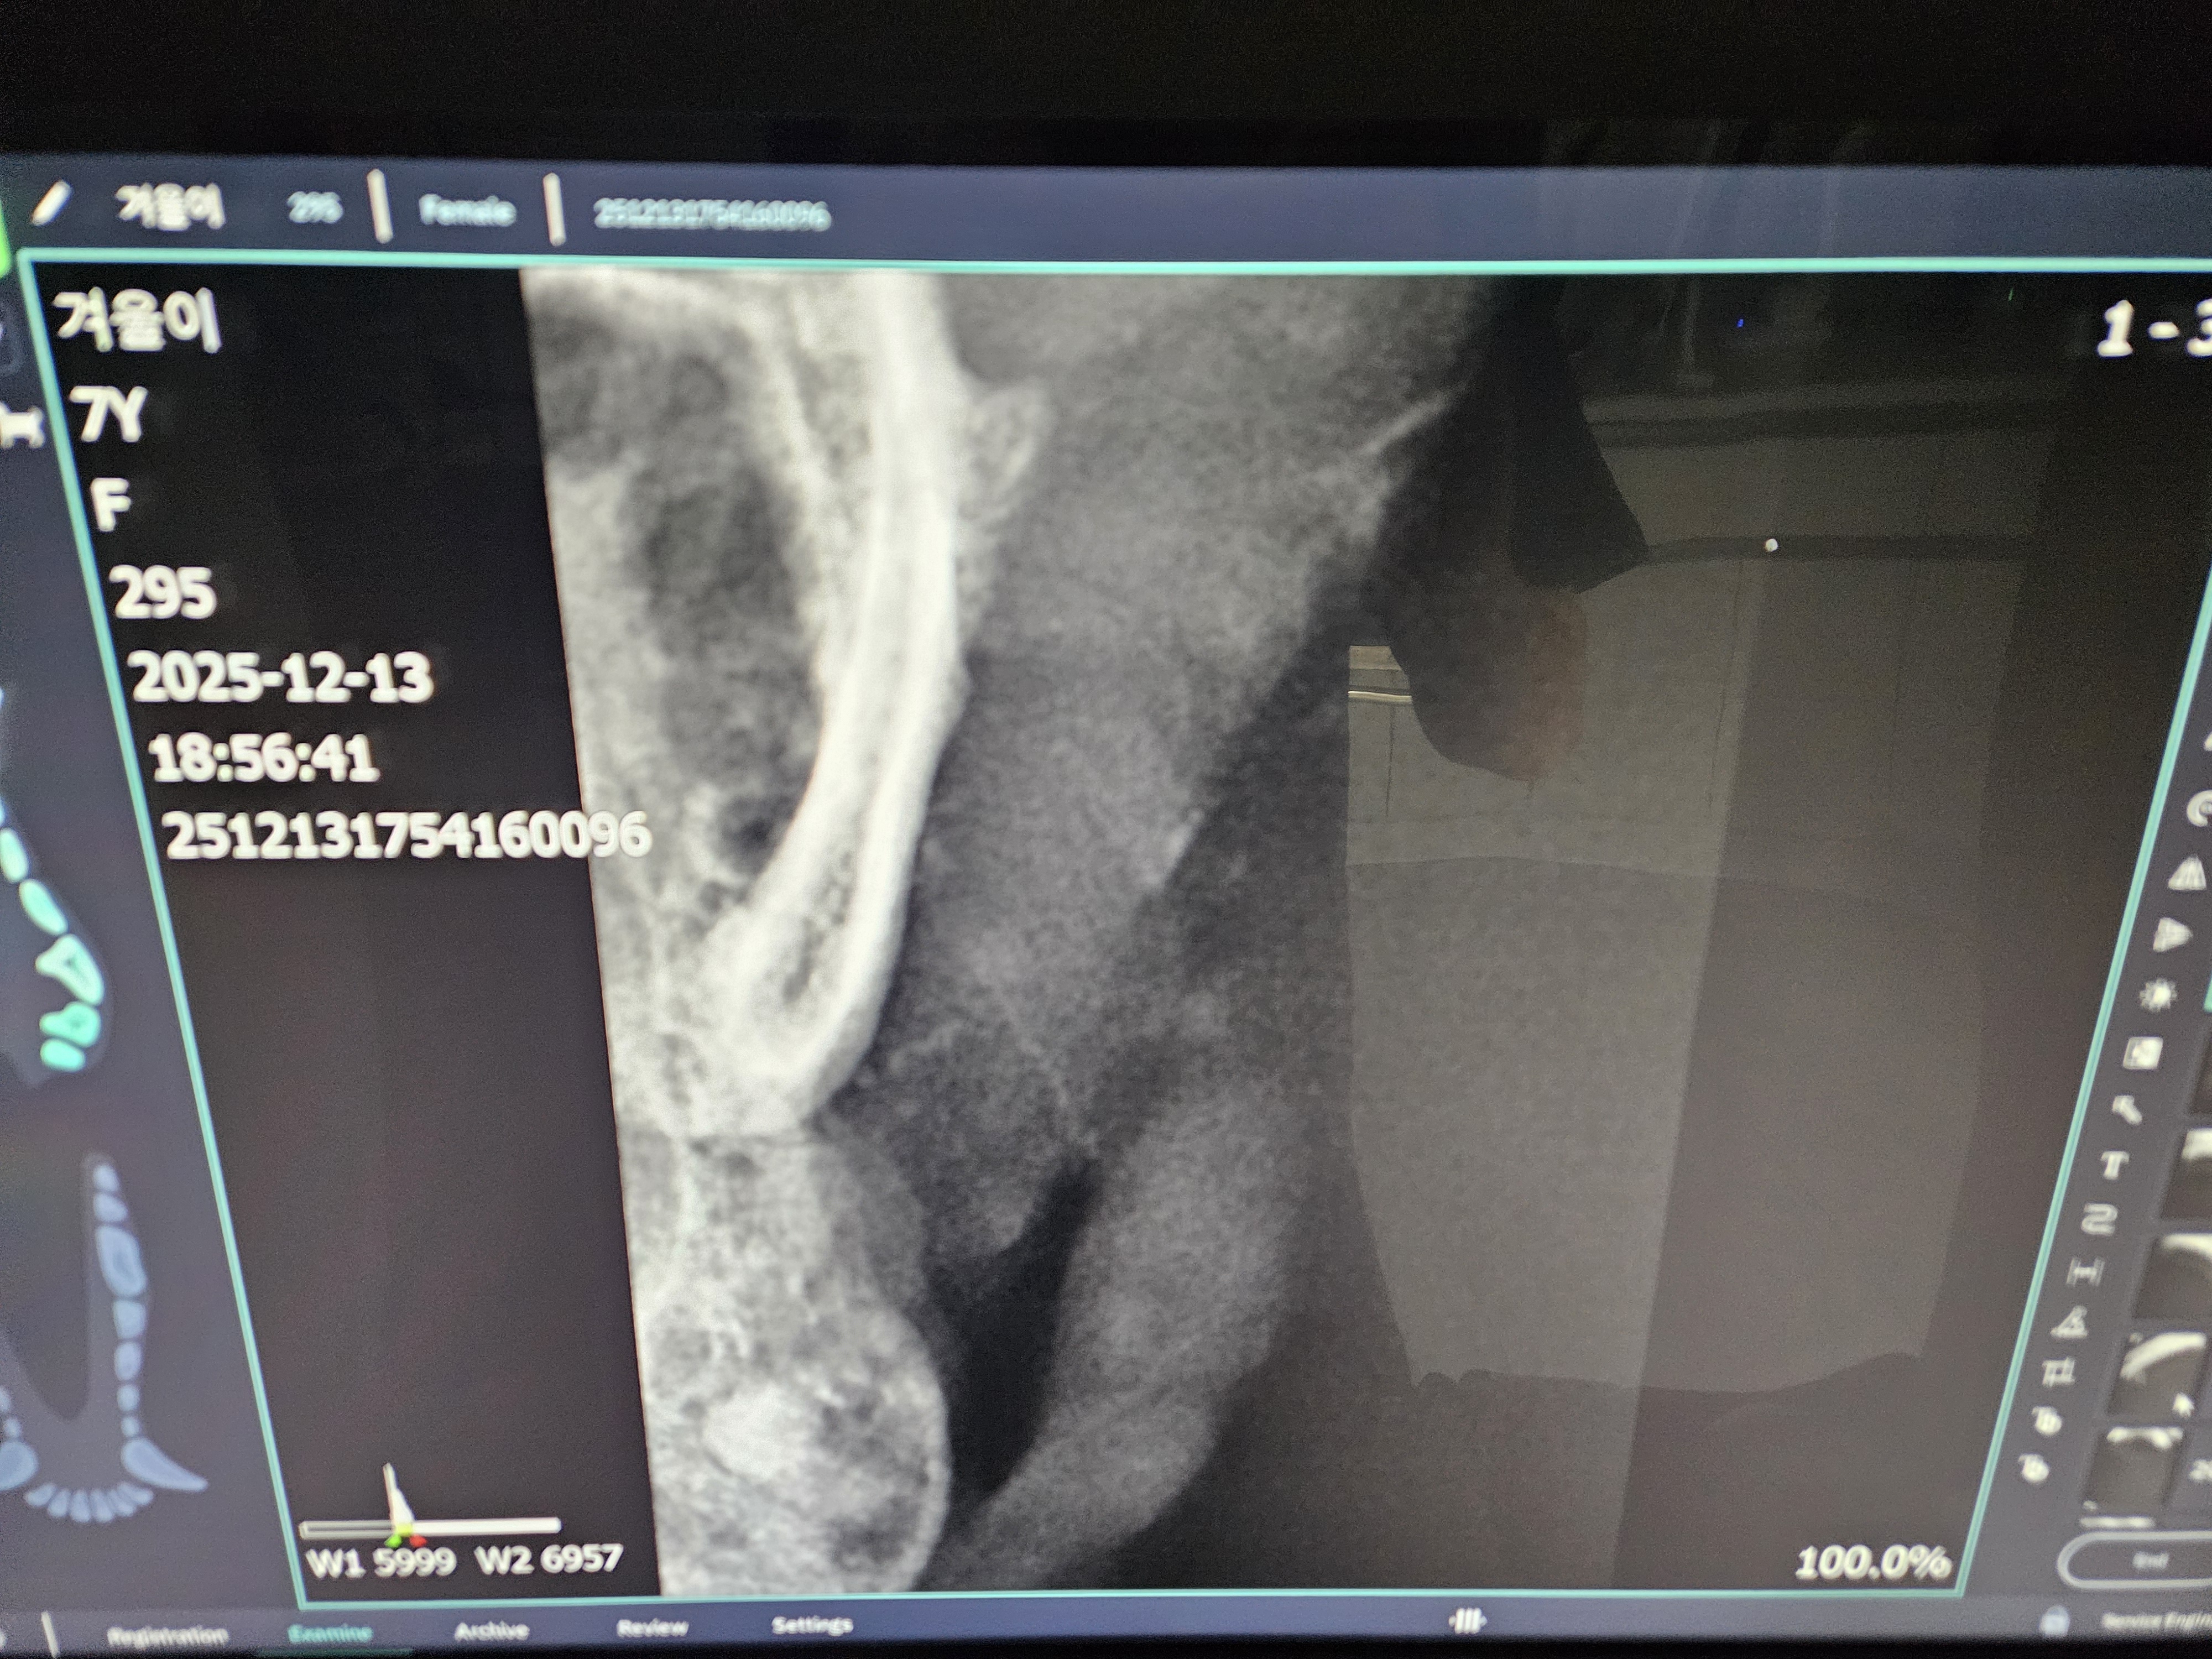

*치아 엑스레이 사진 입니다.

| 치료과정 | 겨울이 염증 수치가 엄청 높았습니다. 보통 정상 수치가 5까지인데 109정도로 엄청 높게 나왔다고 합니다. 염증 수치 같은 경우는 단점이 어떤 부위에 문제가 있는지를 나타내는 수치는 아님. 그런데 겨울이는 구강 안쪽이 엄청 빨개졌었음. 그래서 구내염에 의한 급성염증 수치라고 생각하면 되고, 마취 전에 한 검사는 간수치랑 신장 수치를 체크해주셨는데 콩팥이나 다른 부위는 기능이 정상이라고 하셨습니다. 겨울이 같은 경우는 밥을 잘 못먹었을 뿐이지 간수치나 신장 수치는 특이사항이 없다고 하셨습니다. 겨울이가 입원한 날 빈혈이 너무 심해가지고 수액을 맞았습니다. 그런데 적혈구 개체수도 부족해서 계속 수액을 맞을 수가 없었습니다. 혈액의 적혈구가 부족한혈액이 점점 많아지는 거예요. 항생제 수액으로 마무리 했다고 하셨고,급성 염증 수치는 시간이 지남에 따라서 무조건 좋아진다고 하셨는데, 약은 항생제와 염증 가라앉히는 소염제를 처방해준다고 하셨습니다. 치아 엑스레이 찍은 결과 치조골이라고 해서 이빨에 잡고 있는 뿌리가 어 다 녹아 있었고,그래서 이런 부분들이 이빨의 기능을 상실한 채로 그냥 이가욱씬욱씬한 상태로 있었을거고, 그래서 이빨을 뽑아야 하는 상태라고 하셨습니다. 송곳니는 부러져 있는 부위도 있어서 그런 이빨들은 뿌리 안남기고, 제거를 하셨다고 했습니다. 이빨 자체가 약한 상태이고 전체적으로 발치를 다 한 상태라고 하셨습니다. |